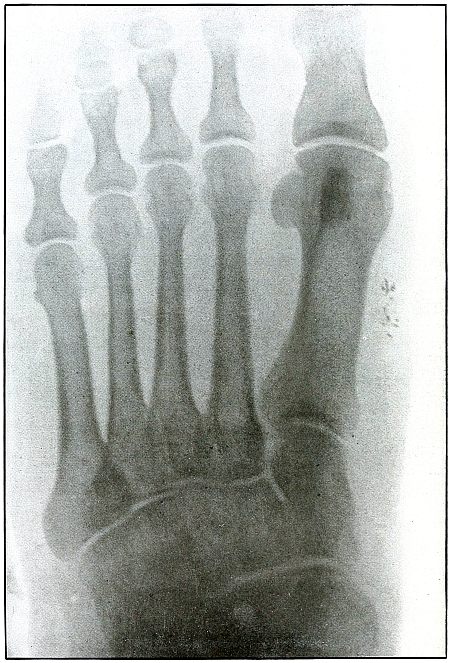

| 154. |

Gunshot wound, foot |

318 |

| 155. |

Gunshot wound, foot |

320 |

| 156. |

Gunshot wound, foot, multiple |

322 |